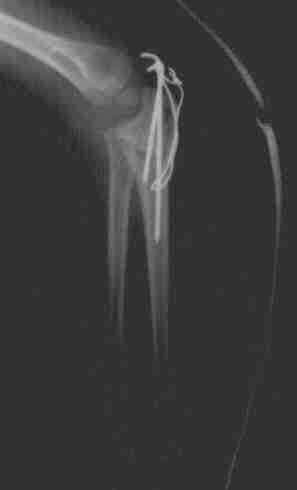

Fractura de codo izquierdo. Pablo, 4 años y medio La misma fractura, vista desde otro ángulo Reconstrucción del hueso (osteosíntesis) llevada a cabo tres días después Aspecto del hueso a los tres meses, después de retirar las piezas metálicas.

Fractura de codo izquierdo. Pablo, 4 años y medio

Reconstrucción del hueso (osteosíntesis) llevada a cabo tres días después